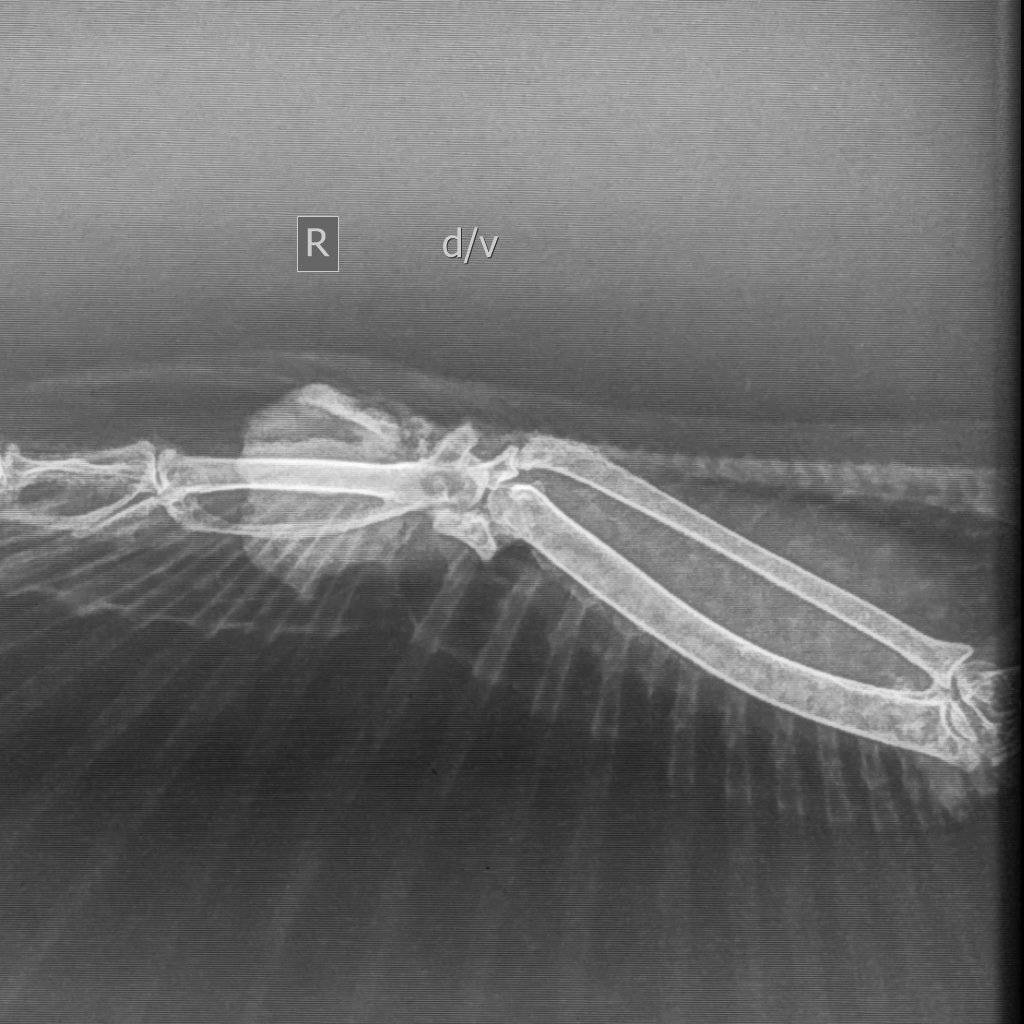

Анастасия Ст. Опубликовано 31 марта, 2025 Автор #6 Опубликовано 31 марта, 2025 Сделали в пятницу рентген в Зоогалерее на Соколе и Демина Григория. София Анатольевна видит здесь еще и зону абсцесса Броди. Но главное - нет проникновения в костную ткань, то есть это не остеосаркома. Будем колоть новокаин с чем-то в корень опухоли и антибиотик в\м. Жду назначений. 1

Cabrera Опубликовано 2 апреля, 2025 #9 Опубликовано 2 апреля, 2025 В 31.03.2025 в 11:06, Анастасия Ст. сказал: Сделали в пятницу рентген в Зоогалерее на Соколе и Демина Григория Не умеет этот человек раскладывать птиц. Прямая проекция у Вас полностью запорота. По ней невозможно оценить состояние внутренних органов. Понятно, что Вас в первую очередь интересовала опухоль, но Вы заплатили за снимок и должны были получить качественный результат, чтобы и состояние внутренних органов тоже можно было оценить. Рентген это один из основных инструментов диагностики и по нему можно увидеть многие проблемы. Опухоль очень похожа на фибролипому. Фибролипома - доброкачественная опухоль. Она имеет тенденцию постепенно увеличивается в размерах, поэтому лучше всего ее хирургически удалить у врача. Только пожалуйста, у кого-то из проверенных специалистов Маркина/Шевченко/Томашевский/Волгина (она сама не оперирует, только в паре с хирургом). Не надо колоть голубю преднизолон, не нужны птице эти эксперименты. Покажите ее очно хорошему специалисту, Вы же в Москве. Не лечите данную птицу на форуме. По поводу антибиотика. Нет таких сроков применения антибиотиков в современной медицине птиц, как 8, 10, 12 дней. Минимально возможный срок приема антибиотика 14 дней, в противном случае Вы просто вырастите резистентную микрофлору и потеряете для дальнейшего лечения все фторхинолоны. При этом даже курс в 14 дней крайне ненадёжен. Когда речь идет об инфекции костей, то это 30+ дней, не меньше.

Анастасия Ст. Опубликовано 2 апреля, 2025 Автор #10 Опубликовано 2 апреля, 2025 (изменено) 4 минуты назад, Cabrera сказал: Не умеет этот человек раскладывать птиц. Прямая проекция у Вас полностью запорота. По ней невозможно оценить состояние внутренних органов. Понятно, что Вас в первую очередь интересовала опухоль, но Вы заплатили за снимок и должны были получить качественный результат, чтобы и состояние внутренних органов тоже можно было оценить. Рентген это один из основных инструментов диагностики и по нему можно увидеть многие проблемы. Опухоль очень похожа на фибролипому. Фибролипома - доброкачественная опухоль. Она имеет тенденцию постепенно увеличивается в размерах, поэтому лучше всего ее хирургически удалить у врача. Только пожалуйста, у кого-то из проверенных специалистов Маркина/Шевченко/Томашевский/Волгина (она сама не оперирует, только в паре с хирургом). Не надо колоть голубю преднизолон, не нужны птице эти эксперименты. Покажите ее очно хорошему специалисту, Вы же в Москве. Не лечите данную птицу на форуме. По поводу антибиотика. Нет таких сроков применения антибиотиков в современной медицине птиц, как 8, 10, 12 дней. Минимально возможный срок приема антибиотика 14 дней, в противном случае Вы просто вырастите резистентную микрофлору и потеряете для дальнейшего лечения все фторхинолоны. При этом даже курс в 14 дней крайне ненадёжен. Когда речь идет об инфекции костей, то это 30+ дней, не меньше. Ничего что я все делаю по рекомендации Зоси? Вы против ее назначений и лечения? Вы сейчас кого критикуете- ее наверное? Изменено 2 апреля, 2025 пользователем Анастасия Ст.